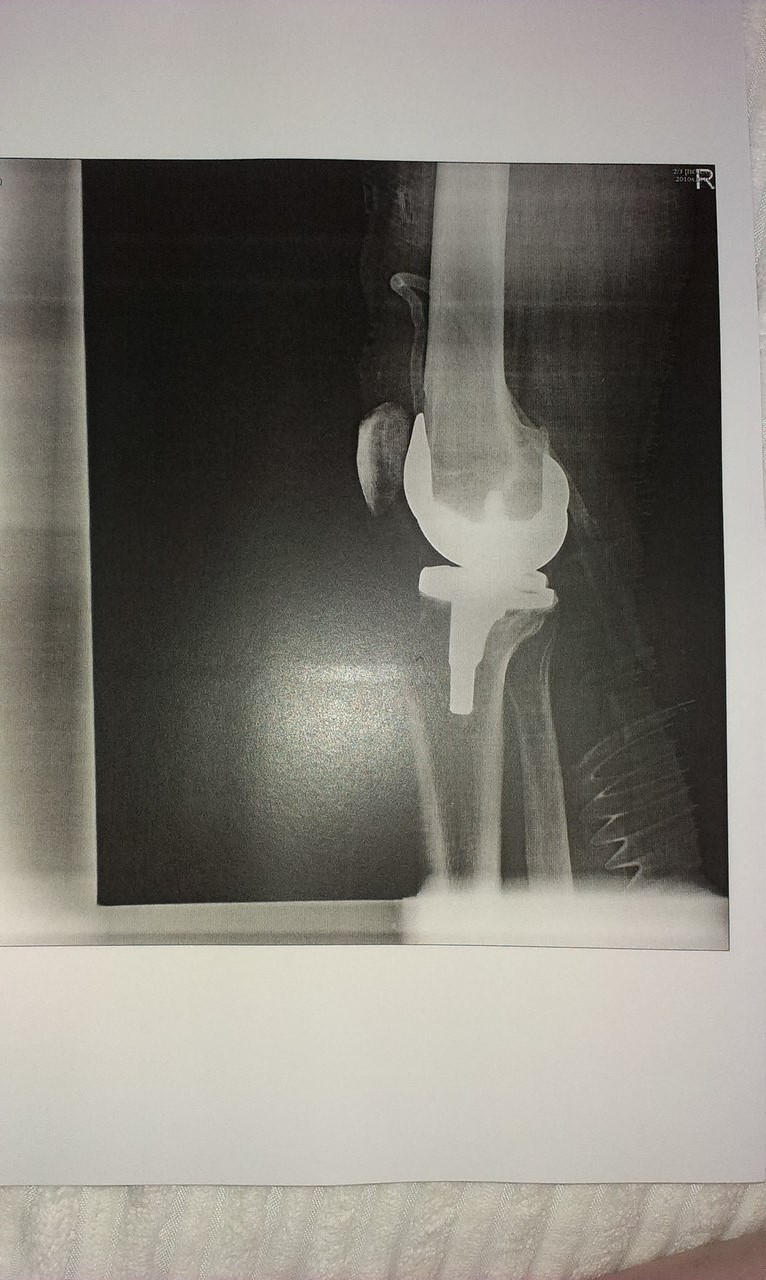

Добрый день! У меня мужу 53 года, эндопротезирование (при гонартрозе 3 степени обеих коленных суставов) с работы уволили по состоянию здоровья, ВВК выдала заключение не годен к работе. Пришли получать инвалидность в МСЭ, нам сказали здоров инвалидность не положена, ходит с палочкой, ноги постоянно подворачиваются, ходить долго не может очень болят, носит компрессионное белье, обязательно фиксирует колени, хотя и проходил реабилитацию, не все процедуры смог переносить, а после еще и хуже  стало. Вопрос положена группа или нет? Благодарю за ответ.

Прикрепления: 6830771.jpg (213.2 Kb) · 5990448.jpg (146.6 Kb) · 4478949.jpg (236.3 Kb) · 6017681.jpg (212.4 Kb) · 8682877.jpg (86.0 Kb)